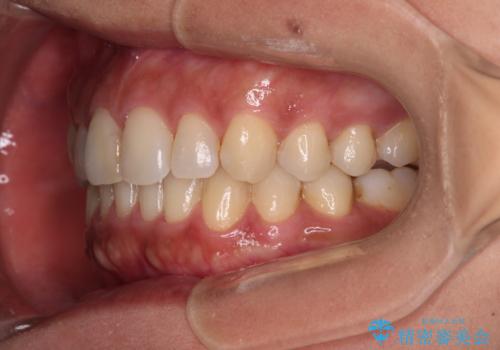

沖縄から飛行機で通院 インビザラインによる矯正治療

- 患者様

- 30代女性

- 矯正装置

- インビザライン

- 治療期間

- 3年8ヶ月

- 定期的に東京に来るので、沖縄から矯正治療で通院したいとのことで来院された患者様です。

歯列不正は軽度であったので、応急処置の少ないインビザラインにて矯正治療を行うこととしました。

通院途中に、仕事の都合で東京に来る機会が激減してしまったため、なかなか治療が進まず、当初終了予定であった時期が2年近くずれ込んでしまいました。